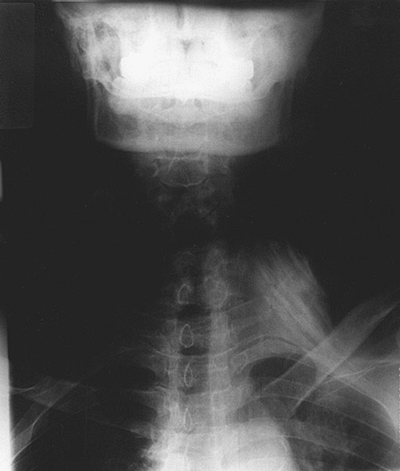

The cricoid cartilage (indicative of the transverse process of C6), the

clavicular head of the sternocleidomastoid muscle, and the anterior and

middle scalene muscles with the interscalene groove in between (Fig. 7-1).

Figure 7-1.

The cricoid cartilage, the clavicular head of the sternocleidomastoid muscle, and the anterior and middle scalene muscles with the interscalene groove in between. |